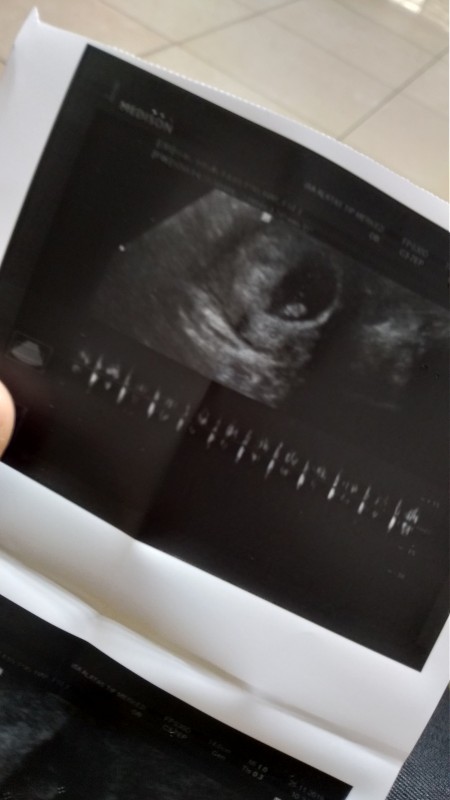

Kızlar merhaba. Daha çok erken biliyorm ama merak ediyorum bebeğimin cinsiyetini. Keseye göre ve bebek konumuna göre cinsiyet tahmini olabiliyormus galiba bana da fikirlerinizi soyler misinz ?

Dogum sonu asagida ve solda erkek nuba göre canim

Nuba göre cikintiyi görmek gerekiyor ramzi teorisine göre bakılabilir suan ve ben tam rahim konumunu anlayamadım farklı açıdan çekilmiş sanki ultrason

Tekrar çekip koydum şimdi

Şuan sağda görünüyor benim kızım da keseye sağdan girmişti canım herşey gönlünce olsun